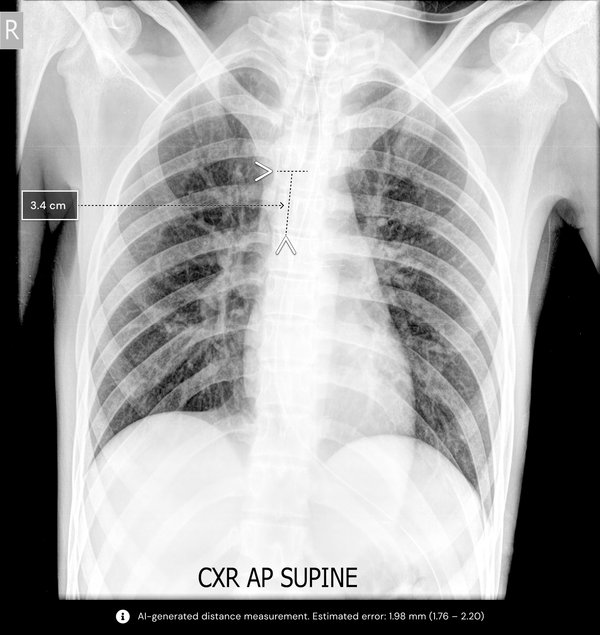

С помощью рентгеновских снимков грудной клетки алгоритм помогает врачам интубированных пациентов определить местоположение дыхательной трубки и автоматизировать измерения. Это первое в своем роде решение, автоматизирующее ручной процесс измерения как для эндотрахеальных, так и для трахеостомических трубок.

Алгоритм Qure qXT-BT анализирует положение трубки, автоматизирует измерения и предоставляет врачу отчет о точности позиционирования трубки менее чем за минуту. Это позволяет врачам быстро определить, правильно ли расположена трубка или требуется дополнительное внимание. Алгоритм не зависит от производителя и предназначен для работы как на портативных, так и на стационарных рентгеновских аппаратах.